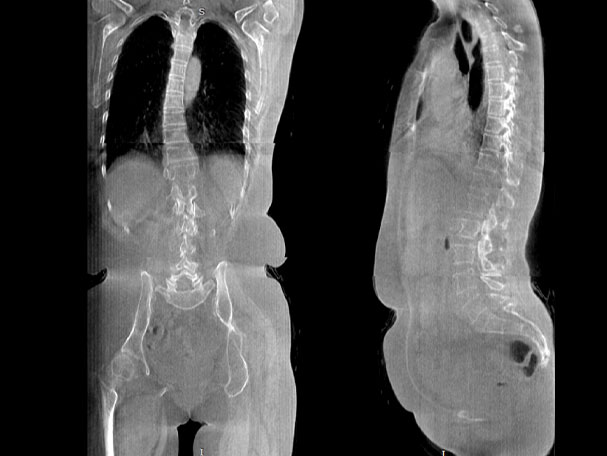

· 补位CT,提供负重位三维影像

· 引领普放走向三维精准诊断时代

填补常规CT/MR空白

助力术前规划和术后评估